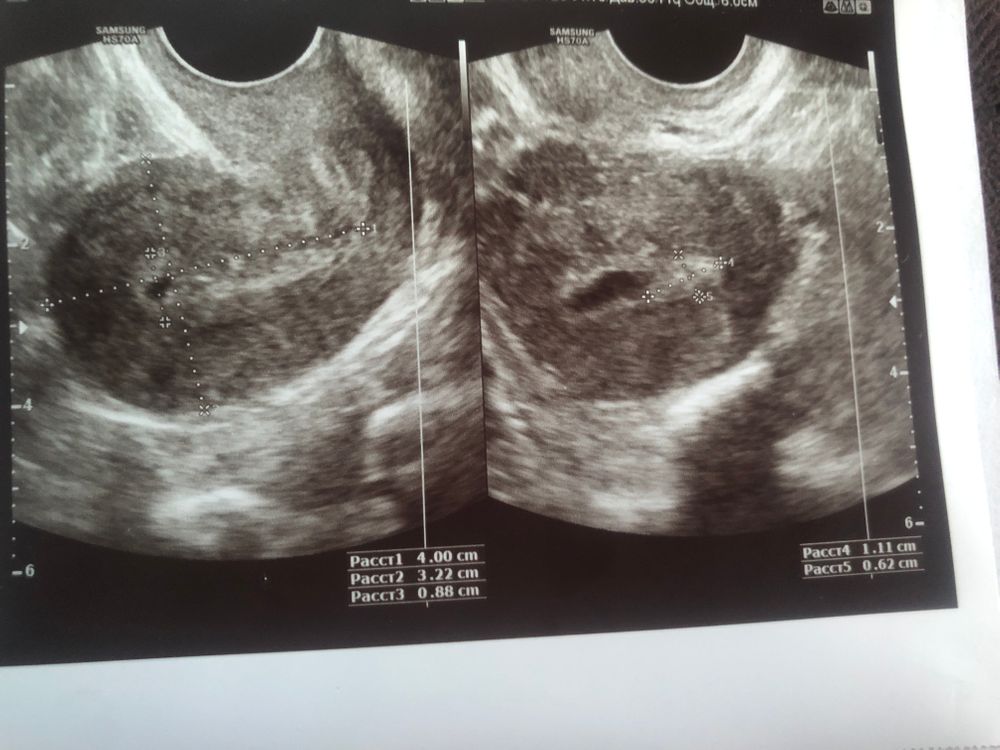

узи 5 дц киста ?

До этого неделю назад сходила на узи так как были боли внизу живота Которые меня беспокоили , Узист Сказала что пока ничего не видно Приходи на 5 дц

Ну вот я сходила На что она мне говорит что все ок Нет особых патологии А яичники говорит работает Идеально

Девушки пожалуйста скажите Это на узи может ли быть киста или Миома ??

Я сама два раза смотрела на полип на мониторе УЗИ. Такой белый червячок, как у вас на фото, на ножке, но я то в движении смотрела, очень хорошо видно на экране, не спутать ни с чем. На фото не понять, может складка, может что угодно.

На фото матка, про кисту тут ничего не скажешь. Но если узист не увидел, даже если киста была, она могла уйти с месячными.